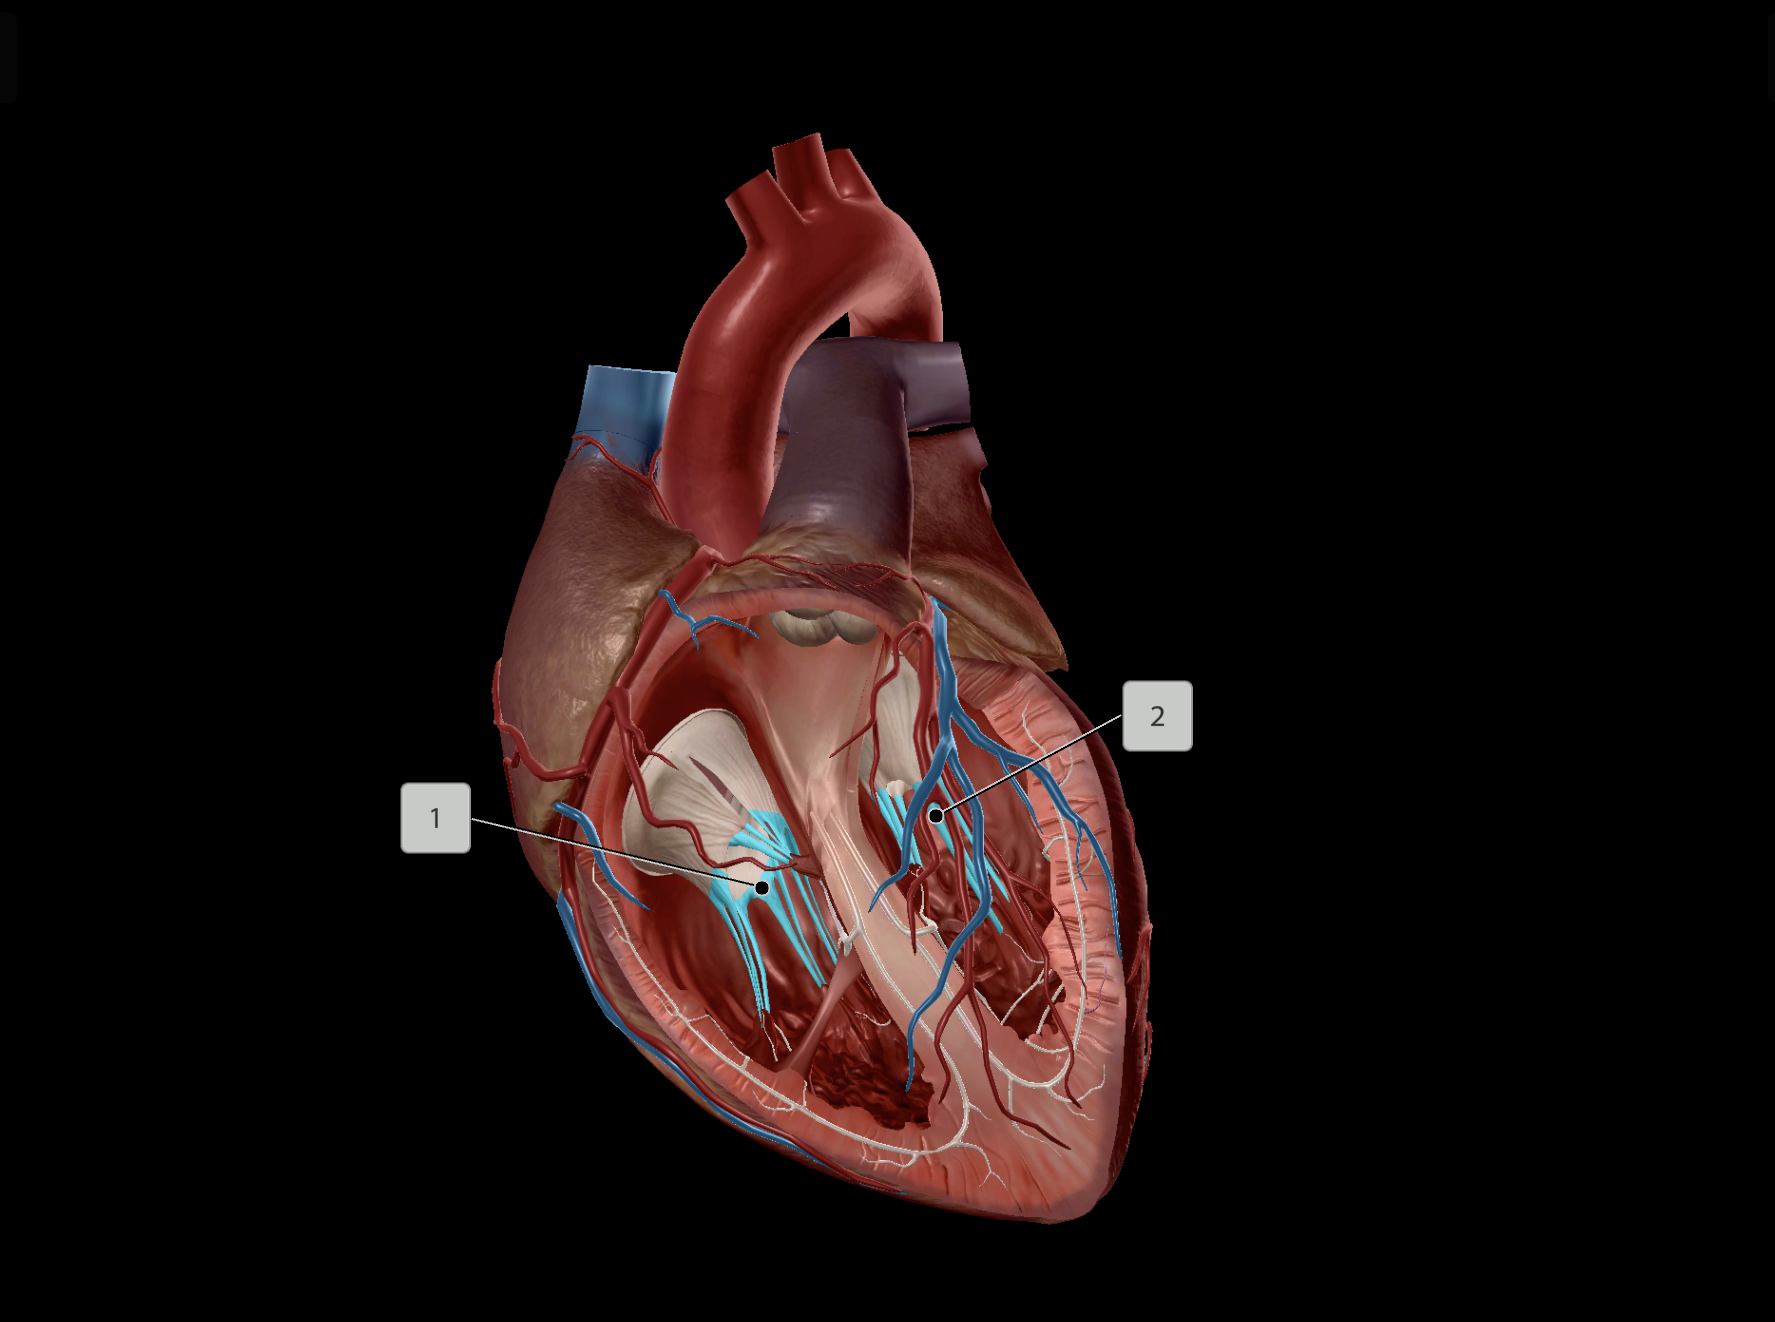

Papillary Muscle

Interventricular Septum

Chordae Tendineae

Anterior Interventricular Artery

Middle Cardiac Vein

Anterior Interventricular Sulcus

Coronary Sulcus

Posterior Interventricular Sulcus/Artery

Coronary Veins

Great Cardiac Vein